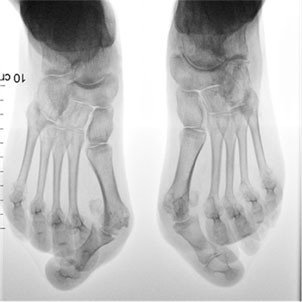

Vorfussdeformität bei rheumatoider Arthritis

Die 42-jährige Patientin leidet seit ihrem 13. Lebensjahr an rheumatoider Arthritis. Schubartige Entzündungen vor allem der Zehengrundgelenke haben im Laufe der Zeit zu Arthrosen dieser Gelenke geführt; durch Beteiligung der Mittelfussköpfchen wurden die Gelenke destruiert. Es hat sich typischerweise ein Spreizfuss mit kontrakten Hallux valgus und Hammerzehendeformitäten entwickelt, weswegen die Patientin Probleme hat, passendes Schuhwerk zu finden. Am Vorfussballen haben sich ausserdem, verursacht durch Druck der Hammerzehen auf die Mittelfussköpfchen, schmerzhafte Schwielen entwickelt; diese Symptomatik wird als Metatarsalgie bezeichnet und erschwert das Barfussgehen.

Die Röntgenaufnahmen beider Füsse zeigen, dass es bereits zu schweren Veränderungen der Zehengrundgelenke gekommen ist. Diese weisen Fehlstellungen auf, die Grundgelenke 2–5 sind ausgerenkt. Die Köpfchen der Mittelfussknochen sind destruiert und weisen Formveränderungen auf. Wenn bei schweren Vorfussdeformitäten Masseinlagen und die Anpassung des Schuhwerkes die Beschwerden nicht mehr ausreichend lindern, ist ein chirurgisches Vorgehen indiziert, die Erfolgsaussichten sind hierbei insgesamt gut.